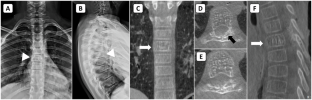

A 14-year-old boy presented with thoracic myelopathy signs. The MRI scan suggests T1 and T2 hyperintense signals within the T6 vertebral body with extramedullary extradural space occupying the lesion. The CT scan showed a “polka dot” appearance. Preoperative endovascular embolization followed by surgical decompression with posterior instrumented stabilization under O-arm navigation and tumor excision was planned. Cystic extradural lesion excised and vertebroplasty done at T6 level. Histopathology slides confirmed hemangioma.

The most common age of involvement is between 30 and 70 years it is rarely seen in the pediatric age group. To the best of our knowledge, fewer than 20 cases of pediatric aggressive vertebral hemangiomas have been reported. Based on a review of pediatric AVH only 4 patients have been treated with preoperative vascular embolization followed by surgical decompression and stabilization. O-arm navigated AVH excision and vertebroplasty has never been described in the literature; this being the first case. It also aids in the identification of tumor margins along with real-time monitoring of adequate resection.